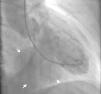

O ecocardiograma transtorácico revelou a presença de pseudoaneurisma/aneurisma ventricular inferior e posterior gigante, preenchido parcialmente por trombo, e condicionando deformação significativa da geometria ventricular (Figura 1; Vídeo 1‐4). Apesar das suas grandes dimensões, o aparelho subvalvular mitral encontrava‐se íntegro, não existindo regurgitação. Dada a dúvida no diagnóstico diferencial, foi realizada ressonância magnética cardíaca que confirmou tratar‐se de aneurisma ventricular gigante (maior eixo de 6,7cm) com trombo no seu interior (Figura 2; Vídeo 5‐6), pelo que iniciou terapêutica anticoagulante. A cintigrafia de perfusão miocárdica exclui isquemia e confirmou necrose do território inferior e posterior. O cateterismo cardíaco pré‐operatório revelou oclusão crónica do segmento proximal da artéria coronária direita e ausência de doença significativa no território coronário esquerdo. A ventriculografia demonstra o volumoso aneurisma ventricular (Figura 3; Vídeo 7). O doente foi submetido a correção cirúrgica do aneurisma: foi observado um volumoso aneurisma da face inferior do ventrículo esquerdo (Figura 4). Após entrada em circulação extracorporal foi feita aneurismectomia parcial com remoção de enorme trombo parietal e encerramento do colo do aneurisma com patch de Dacron® com 2×3cm (Figura 4). O ventrículo esquerdo foi encerrado com sutura contínua. O pós‐operatório decorreu sem intercorrências e o doente teve alta para o domicílio no 5.° dia de pós‐operatório.